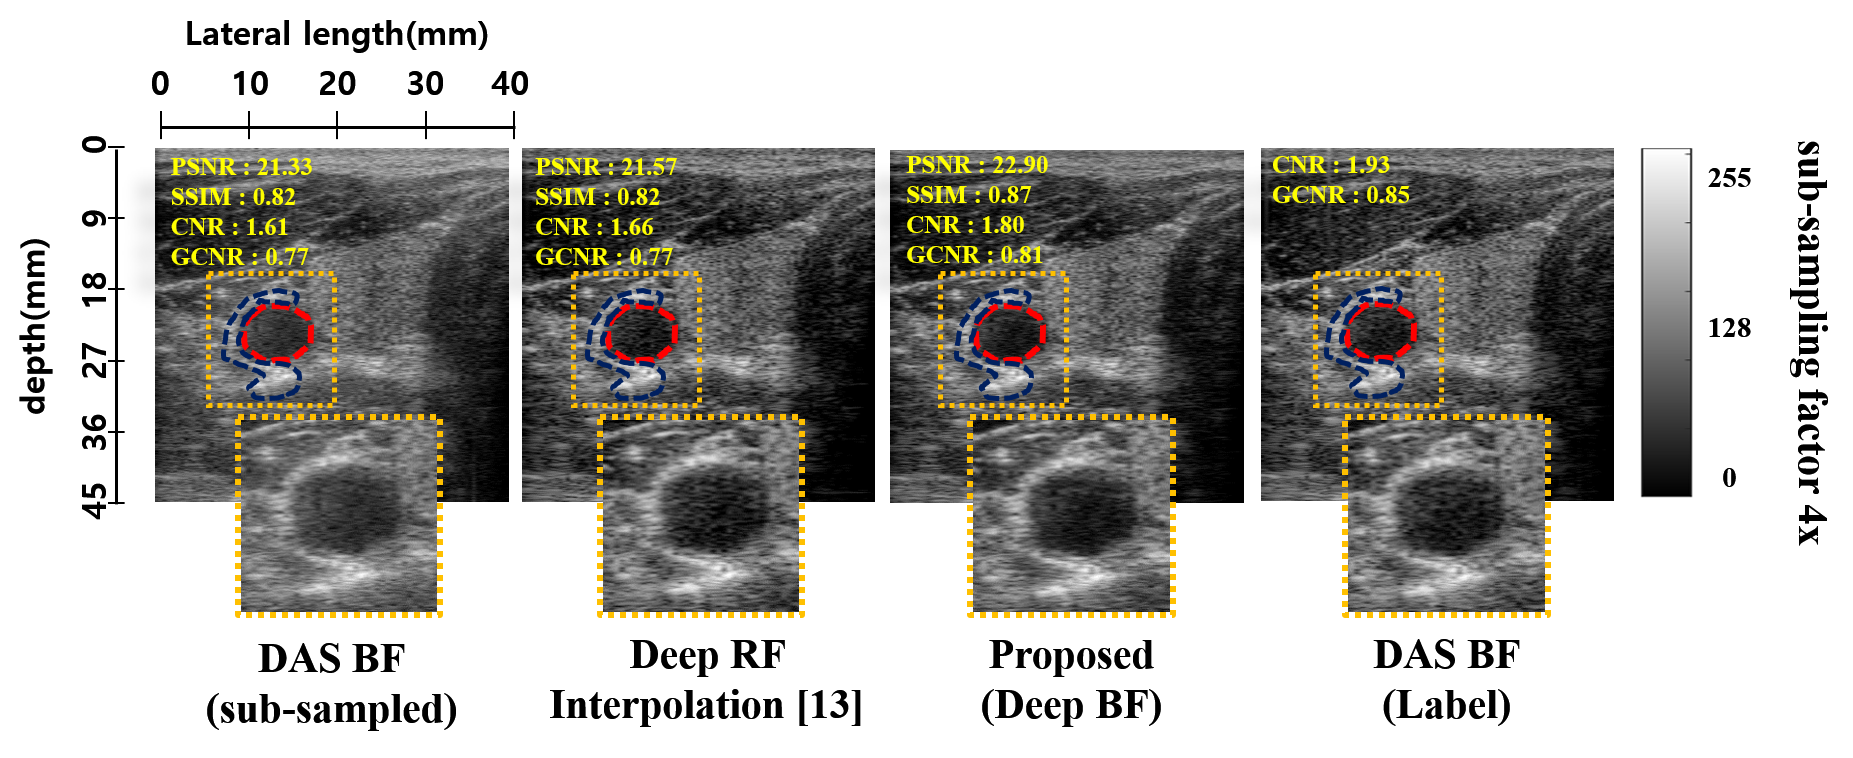

In [13], deep learning approach was designed for interpolating missing RF data, which are later used as input for standard beamformer (BF). On the other hand, the proposed method is an end-to-end CNN-based beamforming pipeline, without requiring additional BF. Consequently, our approach is much simpler and can be easily incorporated to replace the standard beamforming pipeline.

To verify that the proposed DeepBF still outperforms the deep RF interpolation [13], we also compared the CNR, GCNR, PSNR and SSIM distributions of reconstructed B-mode images obtained from in-vivo test frames. Fig. 7 show distribution of aforementioned statistics on 4 sub-sampled in-vivo dataset. From results it can be easily seen that the proposed deep beamformer consistently outperformed the standard DAS beamformer and the Deep RF Interpolation [13]. Specifically, note that on the in-vivo test dataset, the proposed network also outperform the Deep RF Interpolation [13], by and units in CNR and GCNR, respectively. Whereas, in PSNR and SSIM the proposed method achieved dB, units improvement respectively. Fig 6, shows the reconstruction results on 4 sub-sampled in-vivo data using conventional DAS, Deep RF Interpolation [13] and the proposed DeepBF.

In short, the novelty of this work is the end-to-end deep learning to replace the standard BF, which was never considered in [13].

In contrast to [13] where deep learning approach was designed for interpolating missing RF data to be used as input for standard beamformer (BF), the proposed method is an end-to-end CNN-based beamforming pipeline, without requiring additional BF. To verify that the new approach does not sacrifice any performance, we performed quantitative study using test dataset. As shown in Supplementary Material, the proposed network outperform the method in [13] in both CNR and GCNR.